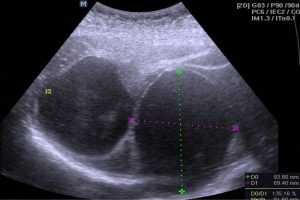

Diplomados en Ultrasonografía